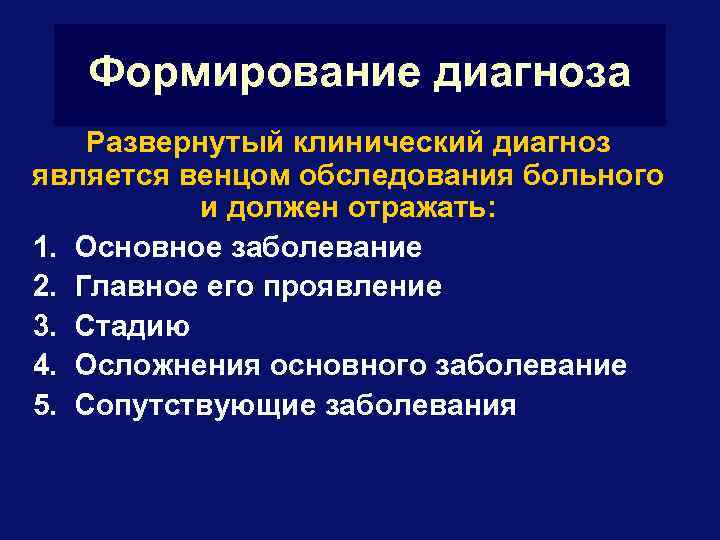

Формирование диагноза Развернутый клинический диагноз является венцом обследования больного и должен отражать: 1. Основное заболевание 2. Главное его проявление 3. Стадию 4. Осложнения основного заболевание 5. Сопутствующие заболевания